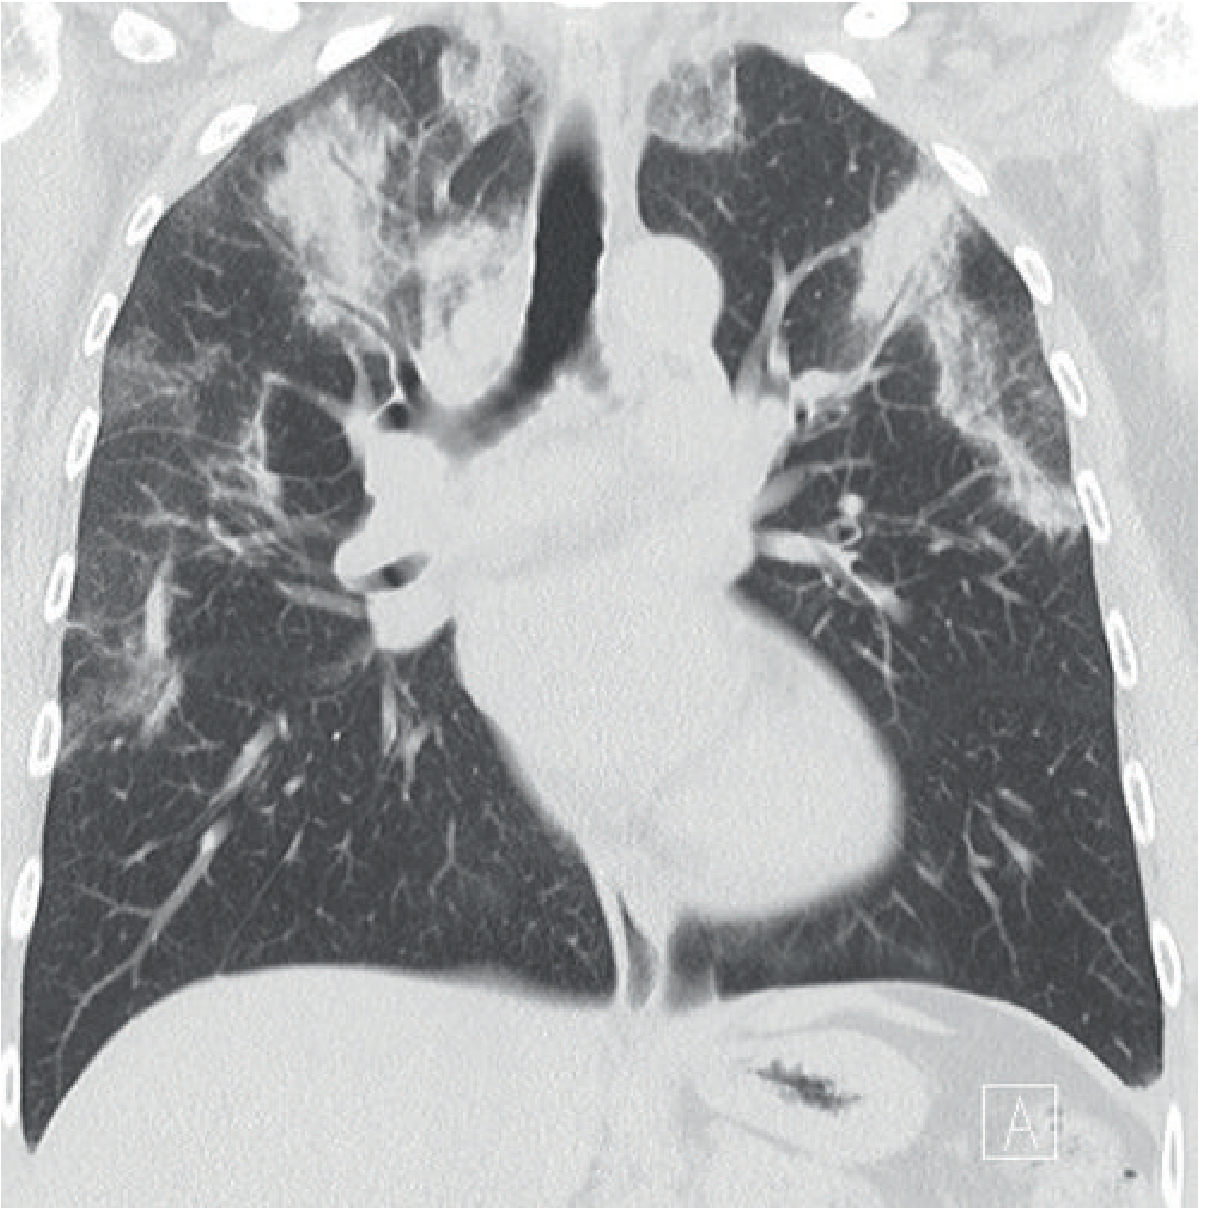

Coronal CT showing "photographic negative of pulmonary edema" pattern — bilateral upper-zone peripheral consolidation in CEP

Fig: Coronal CT reconstruction — upper-zone peripheral airspace opacification paralleling the chest wall in CEP (Grainger & Allison's Diagnostic Radiology)

HRCT (more sensitive and specific)

• Bilateral peripheral opacities in up to 97.5% of cases on HRCT (vs. ~50% on CXR)

• Predominantly upper-lobe distribution

• Both ground-glass opacity and consolidation coexist

• Septal line thickening is common

• Mediastinal lymphadenopathy may be present

• With treatment: consolidation rapidly diminishes → transforms to ground-glass → then streaky/bandlike opacities parallel to chest wall → resolves

Distinguishing from organizing pneumonia (COP): CEP has peripheral opacities without nodules; nodules are seen in 32% of COP but only 5% of CEP.